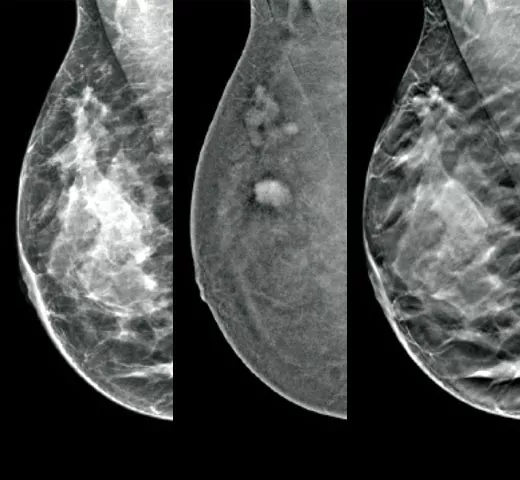

Cutting-Edge Imaging

Optimal cancer detection starts with high quality imaging. Integrate the EUREF-approved1 Hologic mammography technologies into your clinical pathway to maximise efficiency in your imaging workflow.

Confident Cancer Detection

The clinically proven tomosynthesis and contrast enhanced imaging technologies, plus future-proofed AI powered solutions at the point of care, help you make better clinical decisions while accelerating reading time and improving operational efficiency.

Reveal fine details with fast and high resolution 3D Mammography™ exam5 using our advanced detector and innovative 3D™ imaging technologies. These help to detect more invasive cancers with confidence6 With the integration of additional AI-powered solutions, this is a smart platform supporting breast cancer detection, workflow optimisation and risk assessment.

Clarity HD™ High Resolution Tomosynthesis

Producing high-resolution tomosynthesis images normally means slower read times. However, combining Clarity HD high-resolution 3D imaging with Genius AI Detection technology and 3DQuorum allows you to unleash fast and high resolution 3D images,5 accelerating screening and analysis.

Intelligent 2D™ Synthesised Imaging

For higher image quality, more detail, improved read times and low dose, this AI-powered software produces robust, yet natural looking, synthesised 2D images that are well correlated with the 3D mammography data. This enables radiologists to quickly and confidently see subtle mammography features and lesion morphology.

I-View® Contrast Enhanced Imaging